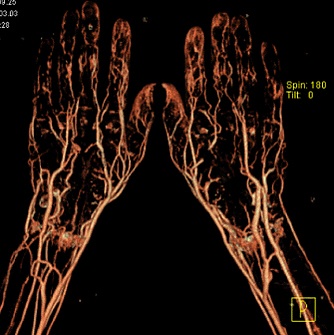

КТ-ангиография позволяет получить послойную серию изображений кровеносных сосудов; на основе полученных данных посредством компьютерной постобработки с 3D-реконструкцией строится трёхмерная модель кровеносной системы.

Спиральная КТ-ангиография — одно из последних достижений рентгеновской компьютерной томографии. Исследование проводится в амбулаторных условиях. В локтевую вену вводится йодсодержащий контрастный препарат в объёме около 100 мл. В момент введения контрастного вещества делают серию сканирований исследуемого участка.